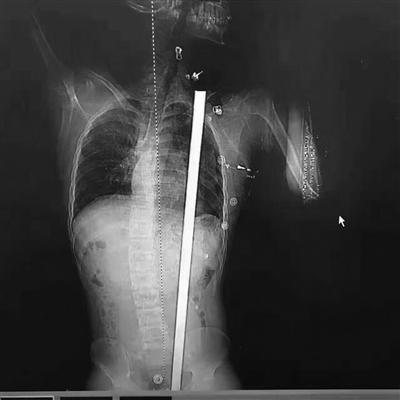

拍片顯示患者體內(nèi)的鋼筋

聞?dòng)嵹s來(lái)的工友們,都被眼前的景象驚呆了。消防隊(duì)員趕到現(xiàn)場(chǎng)后只能將鋼筋的底部鋸斷,而急救人員在第一時(shí)間將小楊急速送往醫(yī)院救治。無(wú)錫市人民醫(yī)院急診外科主任徐進(jìn)宇做了初步檢查后趕緊將他送去CT室拍片,醫(yī)生發(fā)現(xiàn),鋼筋是從他的臀部插進(jìn)去的,根據(jù)工人描述的鋼筋長(zhǎng)度,醫(yī)生做了初步估算,除去露在體外的一截,起碼還有七八十公分長(zhǎng)度的鋼筋進(jìn)入了小楊體內(nèi),可能傷到的器官有膀胱、腸道、胰腺、脾臟等等。而當(dāng)務(wù)之急就是立即手術(shù)將鋼筋取出。“當(dāng)時(shí)患者意識(shí)還算清醒,嘴里不停說(shuō)著 救救我 !毙熘魅位鹚賹⑶闆r上報(bào),醫(yī)院立即組織胸外科、泌尿外科、普外科和麻醉科會(huì)診,準(zhǔn)備手術(shù)。

鋼筋路線沒有觸碰關(guān)鍵要害

“看到CT報(bào)告,我們發(fā)現(xiàn)鋼筋直達(dá)肩胛”。徐進(jìn)宇說(shuō),從報(bào)告上看,鋼筋是從肛門旁進(jìn)入,穿過腹部和胸部,所幸是從脾、胃、腎中間穿過,和心臟擦過,而且沒有傷及大血管。徐主任說(shuō),小楊非常幸運(yùn),這根鋼筋的走線都沒有觸碰到關(guān)鍵要害,如果傷到了致命血管,勢(shì)必造成大出血,病人往往都等不及送醫(yī)。